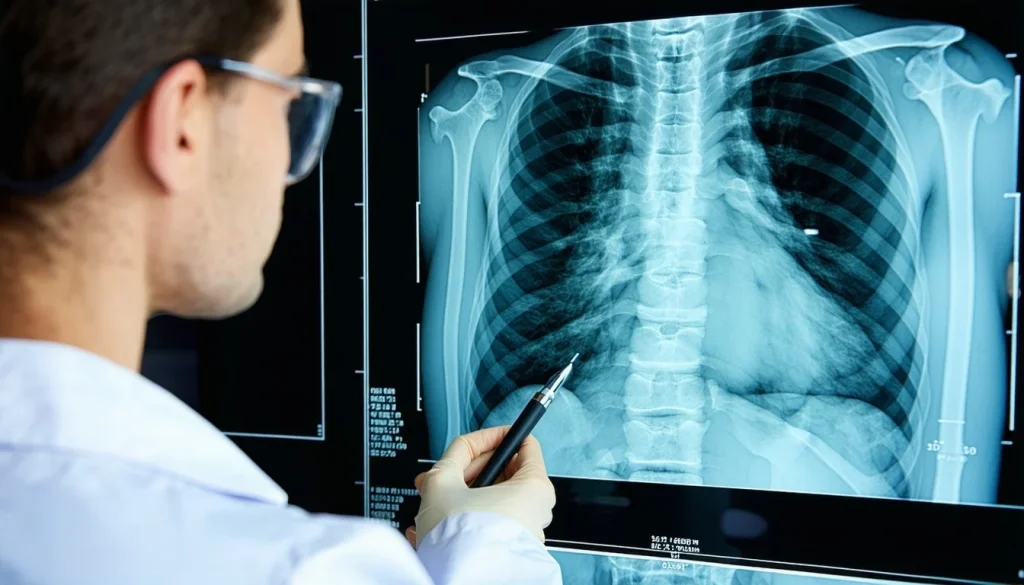

General Surgeons play a pivotal role in medicolegal claims across a variety of scenarios, providing critical expert insights into complex injuries and medical conditions.

Their clinical expertise goes far beyond routine surgical interventions, making them invaluable in assessing causation, prognosis, and long-term impacts of injuries and illnesses in personal injury and medical negligence cases.

General surgeons expertly evaluate injuries arising from:

- Motor vehicle accidents (abdominal and thoracic trauma, traumatic hernias, post-accident complications)